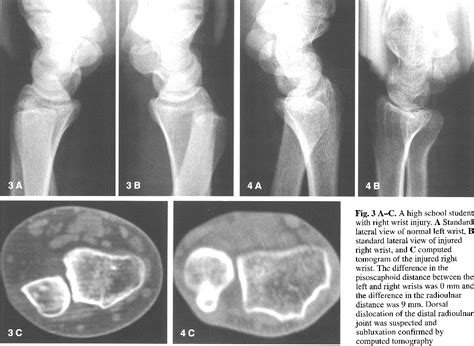

Diagnosing subluxation of radius involves a combination of physical examination and imaging tests. A healthcare provider will typically perform the following steps:

• Physical Examination: The doctor will assess the range of motion, strength, and stability of the forearm. They may also check for tenderness and swelling.

• Imaging Tests: X-rays, MRI, or CT scans may be ordered to visualize the bones and soft tissues. These tests can help confirm the diagnosis and determine the extent of the subluxation.